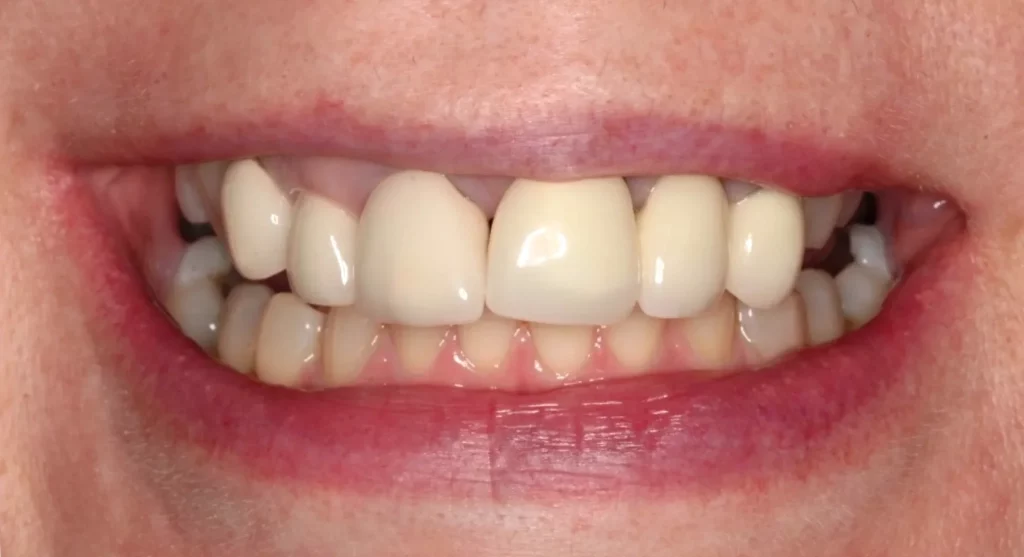

When this lady was younger, she had four teeth removed and then braces placed. However, the patient didn’t like her end smile; she felt it looked too narrow, so she sought more treatment.

At the beginning of treatment, the top gaps were too narrow to place the correct size of the premolar tooth. So braces were put on, and the gaps were opened up. When we achieved enough space, we could place the implants on either side of the top jaw. Porcelain crowns were placed on the implants. A while later, we added composite bonding on other teeth to further improve the patient’s bite, bringing additional comfort to her facial muscles and jaws.